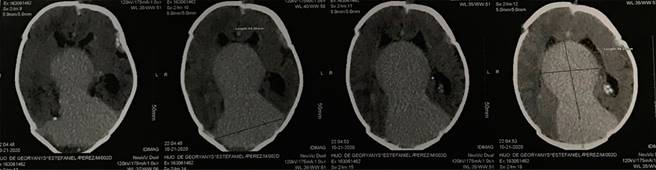

El paciente nació a las 37 SDG mediante cesárea electiva, con buena adaptación neonatal, así como peso y talla normales. Se decidió su trasladó a la Unidad de Cuidados Intensivos Neonatales (UCIN). En la exploración física se encontró macrocefalia, fontanela anterior amplia y normotensa, malformación vascular cutánea de la región frontal izquierda extendida a párpado superior ipsilateral, puente nasal amplio, ausencia de soplos cardiacos, acrocianosis, y con reflejos primarios presentes. Por ecocardiografía Doppler color se detectó hipertensión arterial pulmonar grave, confirmando la dilatación de cavidades derechas y disfunción diastólica del ventrículo derecho. La tomografía de cráneo simple evidenció la MAVG (Figura 2).

Figura 2: Tomografía simple de cráneo. En línea media se observa lesión voluminosa ovoide, con densidad superior al parénquima cerebral, que separa los ventrículos laterales y obstruye el tercer ventrículo. Mide 4.3 × 4.9 cm. Tiene apariencia vascular. Seno longitudinal superior y seno recto se observan dilatados. Imagen compatible con malformación aneurismática de vena de Galeno.